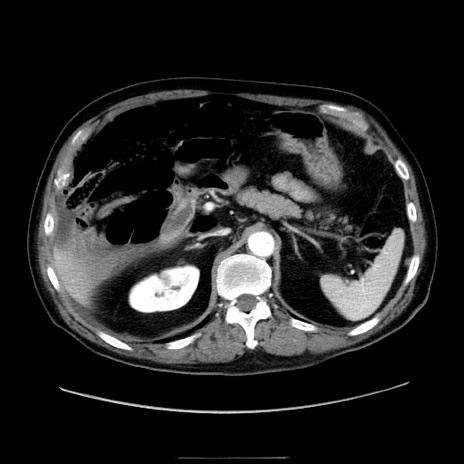

症例30(横断像)

【症例】80歳代男性

【主訴】臍周囲痛

【現病歴】約6時間前から臍下部痛が出現。次第に腹部膨隆・背部痛も生じてきたため来院。背部痛の場所は変化しない。

【身体所見】意識清明、BT 36.3℃、BP  131/87mmHg、P 87bpm、SpO2 100%(RA)、臍周囲自発痛・圧痛あり、反跳痛なし、自発痛部位に一致して板状硬あり、腹部膨隆、腸雑音減弱、CVA tenderness両側陰性。